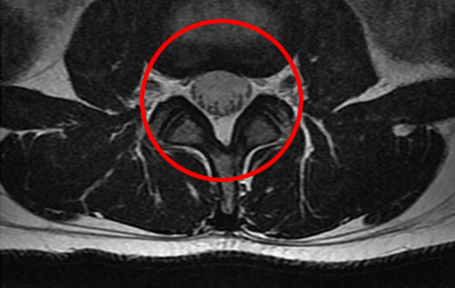

(척추관의 공간이 거의 막혀 있는 상태로,

신경을 압박하여 정상적인 보행이 어려워짐)